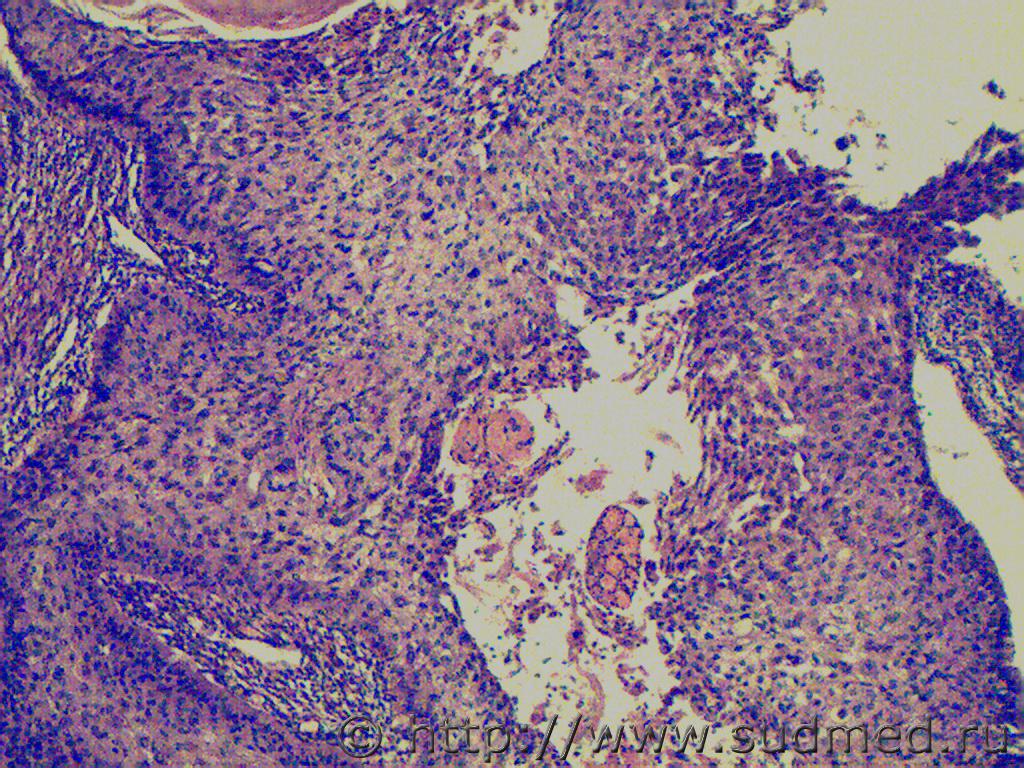

доктор морфолог Добрый день, ув.коллеги! В данном случае наруш... 5.12.2013 - 06:38

Медик Нужно провести ИГХ.

Не стоит.Это труп.К причине см... 5.12.2013 - 11:02![]() ![]() |